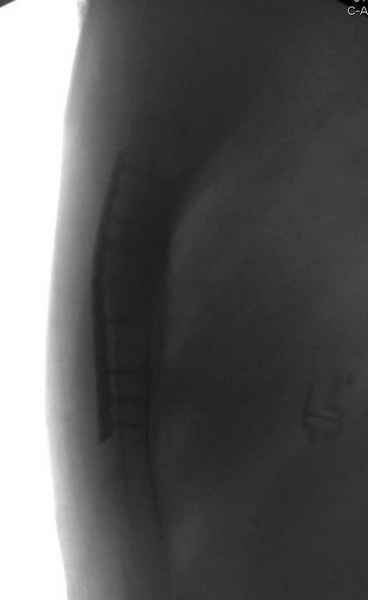

После торакальной операции, по-видимому, сильно натянули проволоку, и в результате получился захлест отломков в друг друга.

А простые посттравматические ложные суставы грудины приходилось оперировать с ограничителем сверла и с фиксацией 2.4 мм пластинами с угловой стабильностью.